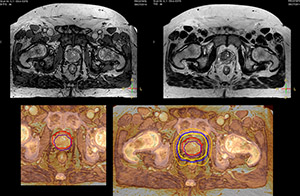

“We currently use MR-RT mainly in the abdomen and pelvis region: prostate, colorectal, pancreatic, cervical, and liver. Also in the brain, we are starting to use it,” says Dr. Yan.

“Using MR, the prostate is well delineated. We quickly see the edges of cancerous tumors like in prostate cancer, and as normal structures can be defined, we can optimize the treatment plan to protect these organs and their normal function. This can potentially improve the outcome. And it improves workflow as well. We can contour more quickly, confident that the tumor is going to be in the field.”

“When a patient registers, first CT simulation and MR simulation are done, followed by CT-MR registration on Pinnacle3. Then the target and normal organ delineation is performed on MR images. Meanwhile we create a reference CT image for online treatment and localization correction. During the treatment phase we can perform additional MRI scans to visualize the anatomy changes and create an adaptive plan. This plan basically adapts the treatment plan to the changes.”